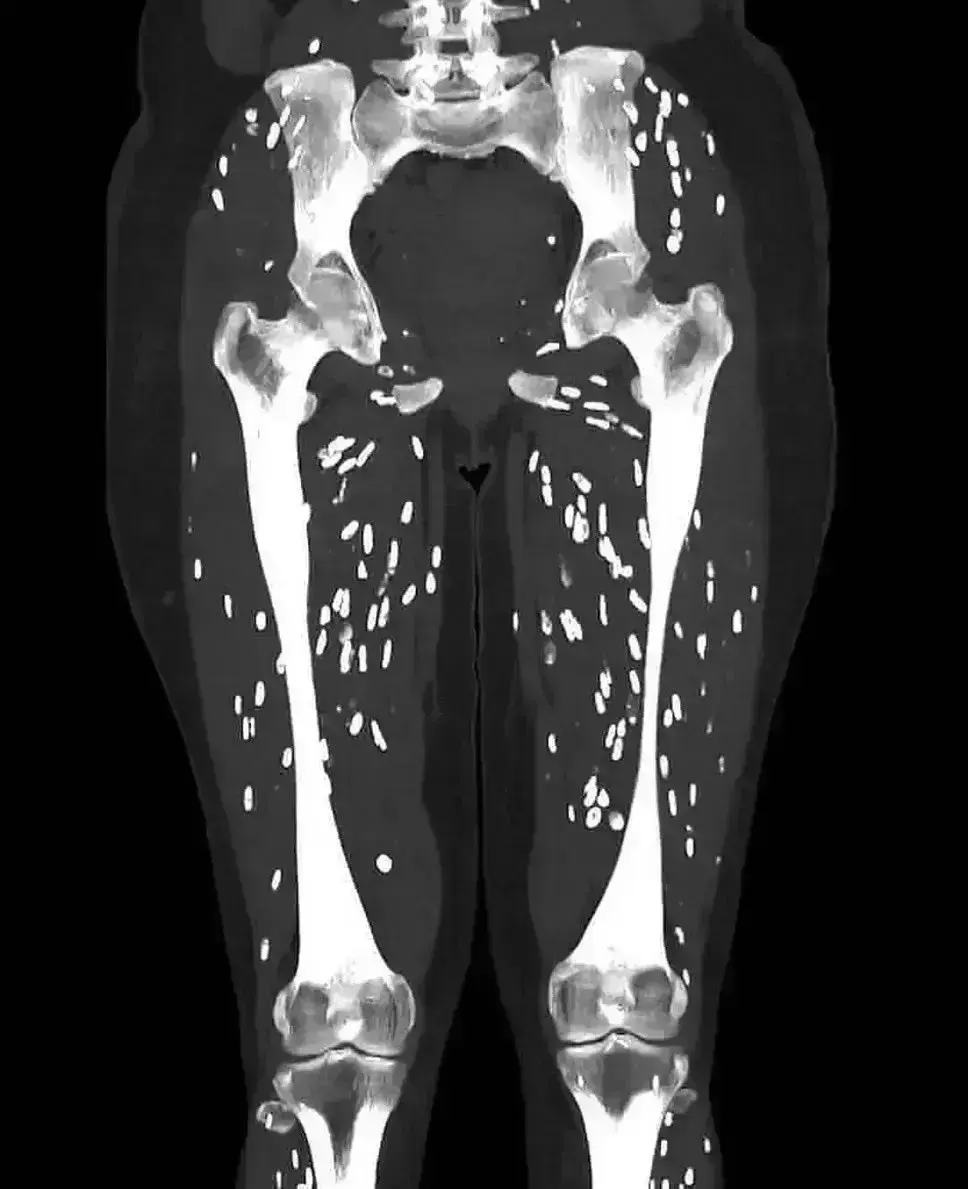

Ο γιατρός των επειγόντων περιστατικών, Δρ. Sam Ghali, μοιράστηκε μια τρομακτική αξονική τομογραφία των μυών των ποδιών ενός ασθενούς με παρασιτική λοίμωξη την Κυριακή στο X.

Θα εμφανιστούν τόσο μικρές λευκές κηλίδες όσο δείχνει η αξονική τομογραφία που μοιράστηκε ο γιατρός και αναφέρονται ως «αποτιτανώσεις κόκκων ρυζιού».